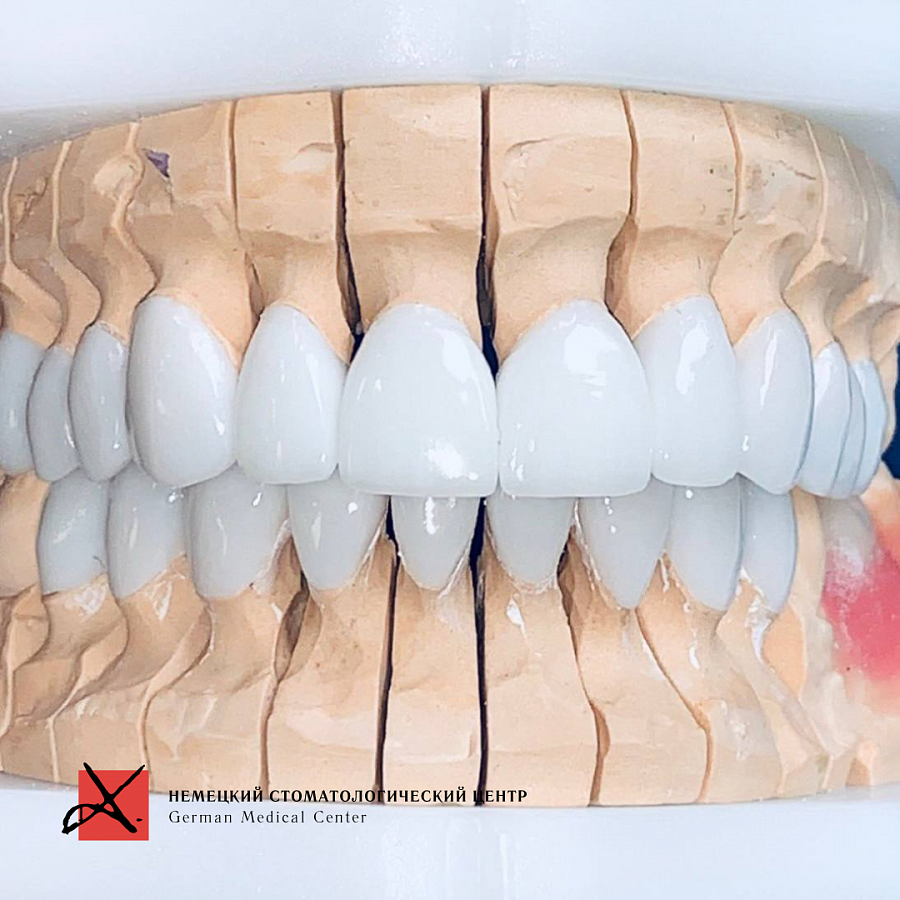

Была проделана работа по удлинению передних зубов и тотальная реставрация с цветом блич 1.